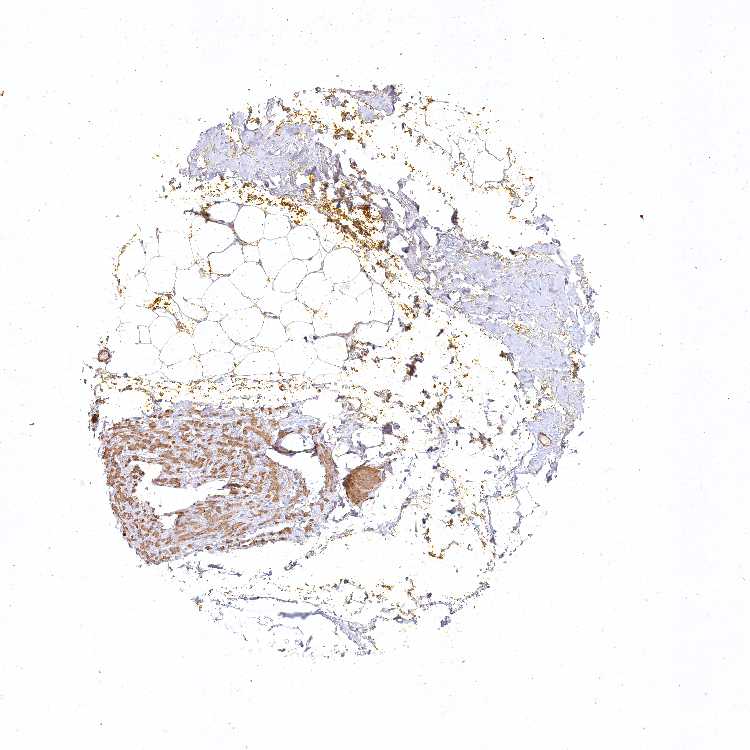

SOFT TISSUE 1 - Antibody stainingi

Antibody staining in the annotated cell types in the current human tissue is reported as not detected, low, medium, or high, based on conventional immunohistochemistry profiling in selected tissues. This score is based on the combination of the staining intensity and fraction of stained cells.

Each image is clickable and will lead to virtual microscopy that enables deeper exploration of all samples and also displays staining intensity scores, fraction scores and subcellular localization as well as patient and tissue information for each sample.

Antibody HPA037681Antibody HPA037682

Fibroblasts MediumNot detected

Peripheral nerve Low-